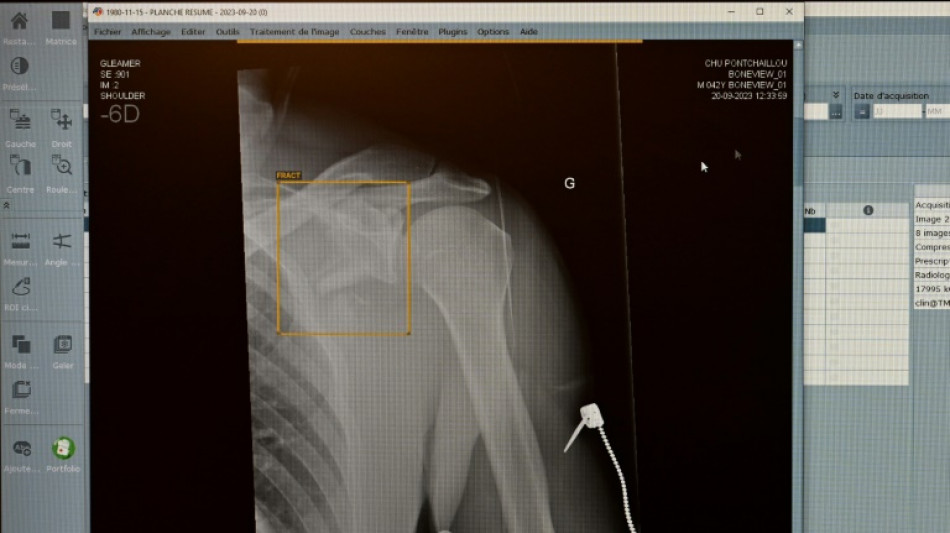

TÜV-Verband: Weniger Röntgengeräte mit Mängeln - Risiken bleiben aber / Foto: © AFP/Archiv

Jedes achte vom TÜV im vergangenen Jahr geprüfte medizinische Röntgengerät hat Mängel aufgewiesen. Die Gutachter stellten an 1893 der insgesamt rund 15.600 untersuchten Röntgengeräte Mängel wie etwa unzureichend gekennzeichnete Kontrollbereiche fest, wie der TÜV-Verband am Mittwoch in Berlin mitteilte. Die höchste Mängelquote wiesen Röntgengeräte in Zahnarztpraxen auf.

Insgesamt sank der Anteil der festgestellten Mängel im Vergleich zum Vorjahr aber von 16 Prozent auf zwölf Prozent. Dennoch fanden die TÜV-Gutachter 2849 einzelne Mängel. "Röntgenstrahlung ist niemals harmlos", erklärte Alexander Schröer, Strahlenschutzexperte des TÜV-Verbands. Geräte müssten daher nicht nur technisch einwandfrei funktionieren, sondern auch korrekt betrieben werden, "um die Strahlenbelastung für Patienten und medizinisches Personal zu minimieren".

Als "besorgniserregend" bezeichnete es der Prüfverband, dass jeder fünfte Mangel (19 Prozent) in die Kategorie der schwerwiegenden Mängel falle. Solche Geräte dürfen erst nach der Beseitigung der Mängel und einer neuerlichen Prüfung wieder in Betrieb gehen.

Gut jedes zweite (54 Prozent) der 2024 geprüften Röntgengeräte entfällt demnach auf die Zahnmedizin. 15 Prozent davon wiesen mindestens einen Mangel auf. Am häufigsten fielen ein mangelhafter Patientenschutz und unzureichend gekennzeichnete Kontrollbereiche auf, die dem TÜV zufolge aber wichtig zur Vermeidung unbeabsichtigter Strahlenexposition sind.

Die Mängelquote von Röntgengeräten in der Humanmedizin lag bei 13 Prozent und betraf etwa Bildwiedergabesysteme. Fehlerhafte Bildwiedergabesysteme gefährdeten die Diagnosesicherheit und könnten zu Fehldiagnosen oder unnötiger Strahlenbelastung führen. Die Mängelquote in der Veterinärmedizin lag ebenfalls bei 13 Prozent.